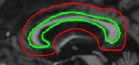

Refer to captionRefer to captionRefer to captionRefer to captionRefer to captionRefer to captionRefer to captionRefer to captionRefer to captionRefer to captionRefer to captionRefer to caption\begin{array}[]{cc}\includegraphics[width=112.0187pt]{lv-2-init.pdf}&\includegraphics[width=112.0187pt]{lv-2.pdf}\\ \includegraphics[width=112.0187pt]{lv-3-init.pdf}&\includegraphics[width=112.0187pt]{lv-3.pdf}\\ \includegraphics[width=112.0187pt]{lv-1-init.pdf}&\includegraphics[width=112.0187pt]{lv-1.pdf}\\ \end{array}

Figure 15: Segmentation of left ventricle wall of the heart in an MR image taken from [42]. Left column shows initialization and right column shows converged result.

We next develop templates for objects with hole(s) in their structure. These templates are called ring templates. Figures 15 and 16 show examples of ring templates. The area enclosed between the red contours act as region 1subscript1\Re_{1} and the area between the green contours is region 0subscript0\Re_{0}. Figure 17 shows the construction of the ring contours. The two seemingly unconnected contours are actually one connected contour. Hence, partial derivative calculations in equation (26) are still valid.

In Figure 15, the ring template has been used for segmenting the left ventricular (LV) wall of heart in cardiac MR images. Another example is shown in Figure 16. The template used in both examples has a greater thickness in the inner ring-shaped annular region than the outer annular region. This was done to facilitate obtaining the desired object’s structural information by means of the contrast (for example, between the endocardium and the LV wall) that a good initialization can offer. Hence, while designing a template, we can incorporate prior knowledge of the object and its surroundings.